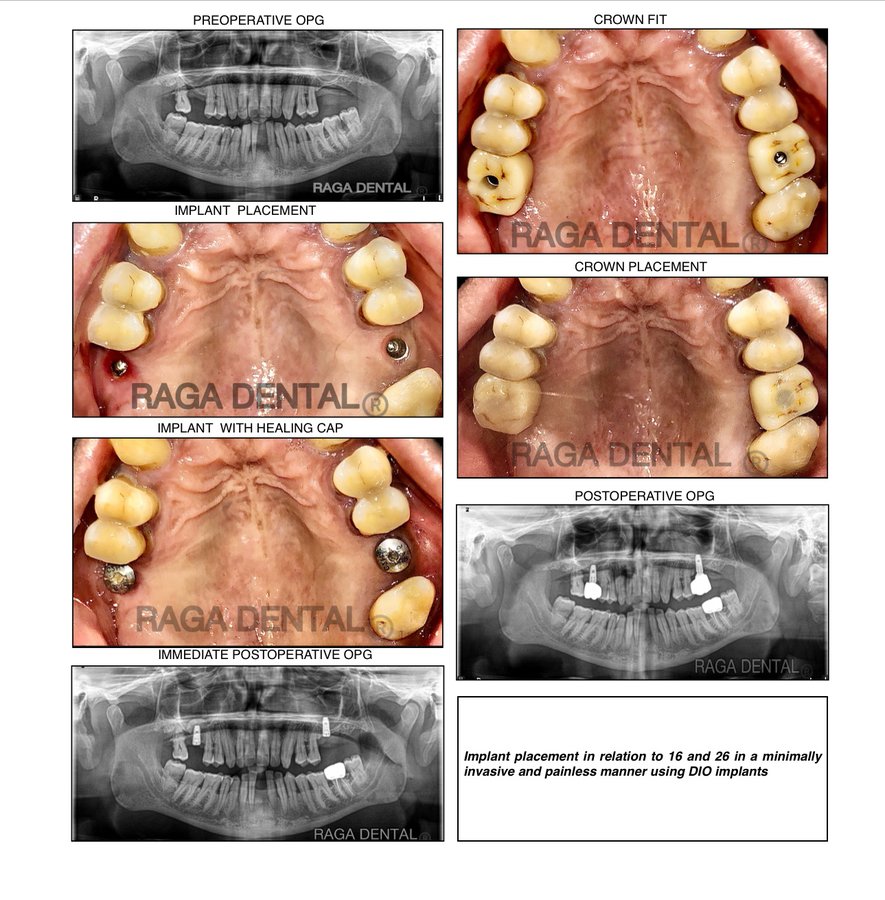

About Raga Dental Center for Dental Implants & Laser Raga Dental is a well established facility with experienced team of doctors , state of the art equipments and especially renowned for Implantology and waterlase Laser Dentistry. We are well equipped with Waterlase Laser, Navident for Navigation implant surgeries, 3D printer for Guided implant surgeries, Phillips zoom whitening for esthetic rehabilitation. We also excel in other ... (Show more)